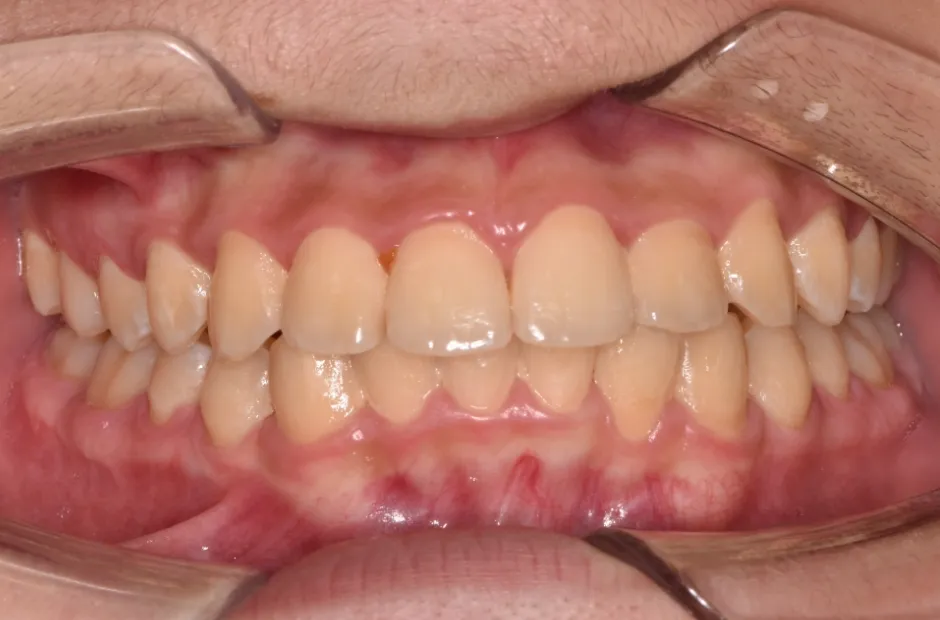

ブラケット矯正

前歯部反対咬合

| 診断名・主訴 | 前歯部反対咬合 |

|---|---|

| 年齢・性別 | 14歳・男性 |

| 治療期間・回数 | 1年2か月 |

| 治療に用いた主な装置 | ブラケット矯正 |

| 抜歯部位 | なし |

| 治療費 | 60万円(税抜) |

| リスク・副作用 | 装置による違和感・疼痛・歯肉退縮・歯根吸収・虫歯のリスクなど |

治療後